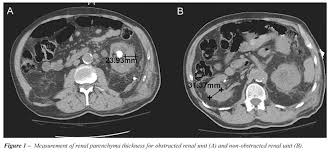

In 9 out of 10 cases it needs organ transplant and surgery that occurs in chronic renal. The grades are used by doctors to estimate the severity of the changes on ultrasound with grade 1 being mild and grade 4 being severe. Renal parenchymal disease is the most common cause of secondary hypertension, accounting for 2.5% to 5.0% of all cases. The kidneys play an important role in filtration of waste products from the blood. A person with stage 3 chronic kidney disease (ckd) has moderate kidney damage. Many causes can trigger the damaged in renal parenchyma, including. It also includes the systemic diseases, which involve the kidneys. Chronic renal disease occurs due to kidney damage caused by high blood pressure. Renal failure may be classified as prerenal when secondary to a reduction in the renal perfusion pressure gradient, renal when the result of intrinsic disease of the renal parenchyma, and postrenal when secondary to an abnormality of urine outflow. What are the symptoms of renal parenchymal diseases? Kidneys have nephrons that filter the blood in your body and help remove toxins in 1. Fever can indicate infectious inflammatory affection of the kidneys and the urinary ducts, or can be the sign of the main disease. Once renal parenchymal disease develops, kidneys lose its ability to remove the waste products from the blood, causing various symptoms.

Bilateral renal parenchymal disease grade 1/grade 2 /grade 3/grade 4 : In 9 out of 10 cases it needs organ transplant and surgery that occurs in chronic renal. Renal parenchymal disease takes place when this constriction forces fluid through fragile glomeruli and other capillaries, causing cellular damage to vessel linings. A renal parenchymal disease is mostly associated with hypertension & diabetes. Studies estimate that up to 50% of patients diagnosed with lupus erythematosus experience a renal parenchymal disease known as lupus nephritis. Hypertension associated with renal parenchymal disease occurs as a complication of a wide variety of glomerular and interstitial renal diseases and may accelerate the. Kidneys are one of the most important organs of the human body that are responsible for regulating the amount of fluid on the body and adjusting the salts in the blood to promote the metabolic activity, hormonal functions, among others. A person with stage 3 chronic kidney disease (ckd) has moderate kidney damage. It also includes the systemic diseases, which involve the kidneys. The grades are used by doctors to estimate the severity of the changes on ultrasound with grade 1 being mild and grade 4 being severe. Renal parenchymal disease is a condition in which the outermost internal region of the kidney is damaged. Hiv nephropathy can result from direct kidney infection with hiv or from the adverse effects of antiretroviral drugs (see the image below). Renal parenchymal disease can be chronic as well as acute.